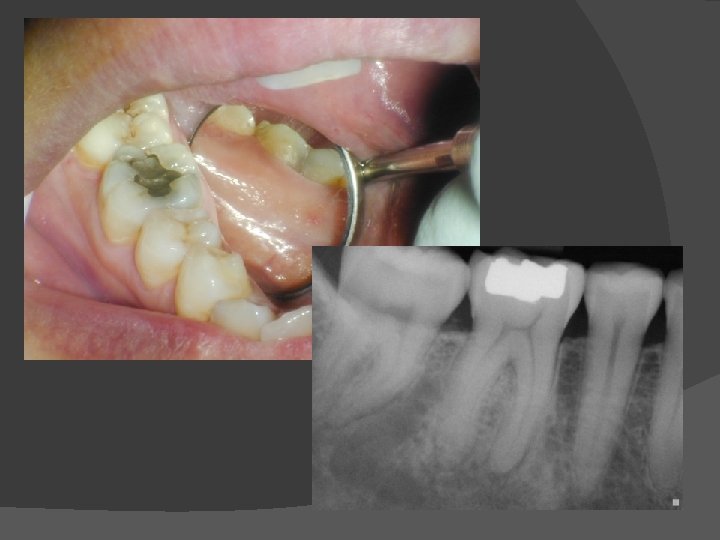

Fractures in Teeth Two Forms: 1. Cusp Fractures 2. Cracked teeth

Fractured Teeth Cracked Tooth Syndrome (CTS) An incomplete fracture of a vital posterior tooth that occasionally extends into the pulp. n Cusp Fractures • Cusp restore vs. Endo/Crown

Transillumination � Helps identify crown fracture Virgin Tooth ! � Fractured Segments of a crown DO NOT transmit light similarly Difficult to use with restored teeth n. Document What You SEE! u. Inconclusive, Possible, Probable, Definitive u. Cuspal Fracture +/or Cracked Tooth n

Cracked Teeth • Need for immediate cuspal protection • Pulpal status (Reversible vs. Irreversible symptoms) determines whether endo is needed or not. Maybe elective endo? • Deep pocketing associated with crack –->POOR PROGNOSIS !

Vertical split root diagnosis Coronal fractures extending into PDL � Perio probing into sulcus depth � Epithelium follows root crack � Frequently cause pulp death � May be result of restorative procedures and/or occlusal stress (Bruxism) � 3/3/2021 Fac. Dentistry - Univ. MB

Photo Dr. Uziel Blumenkrantz